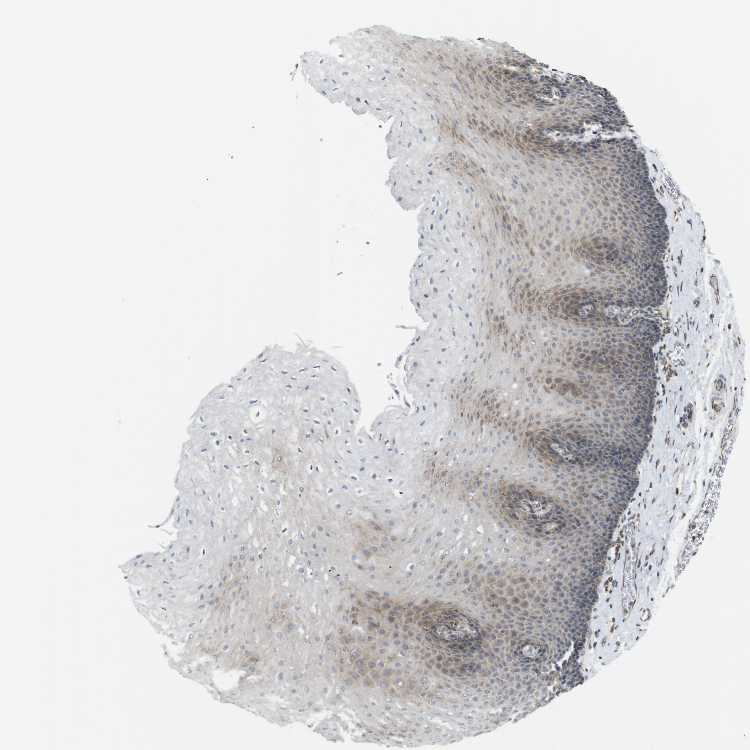

ESOPHAGUS - Antibody stainingi

Antibody staining in the annotated cell types in the current human tissue is reported as not detected, low, medium, or high, based on conventional immunohistochemistry profiling in selected tissues. This score is based on the combination of the staining intensity and fraction of stained cells.

Each image is clickable and will lead to virtual microscopy that enables deeper exploration of all samples and also displays staining intensity scores, fraction scores and subcellular localization as well as patient and tissue information for each sample.

Antibody HPA012761Antibody HPA015127

Squamous epithelial cells LowNot detected